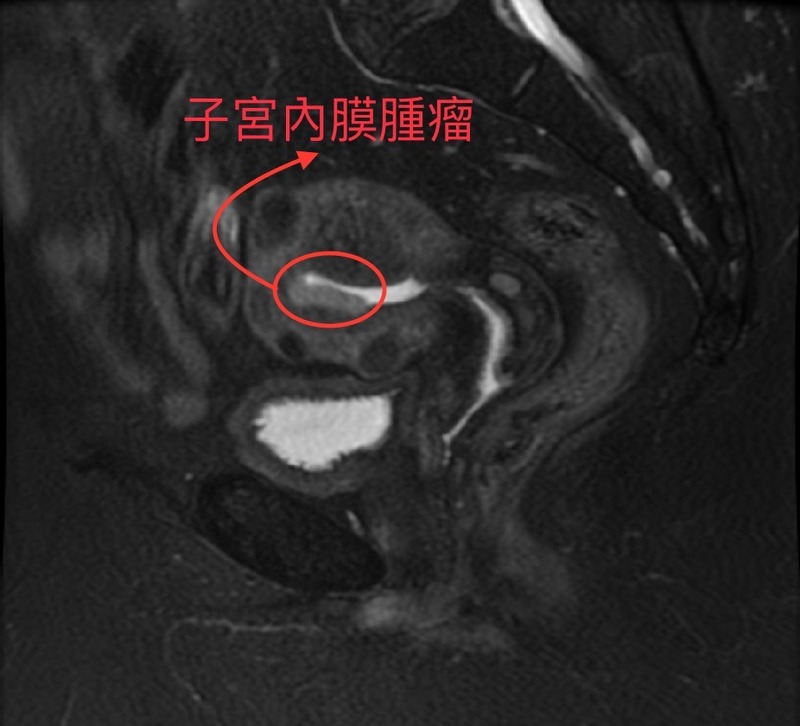

經核磁共振造影(MRI)檢查,李佩蓁醫師指出,癌細胞並未轉移,再經以微創手術取出腫瘤後,也確認腫瘤局限於子宮內膜,屬第一期子宮內膜腺癌,且分化良好,病人在手術後一週出院,不需進行化學治療或放射性治療,後續僅需定期回診追蹤、抽血檢驗腫瘤指數,。

圖說:子宮內膜腫瘤核磁共振造影(MRI)影像。